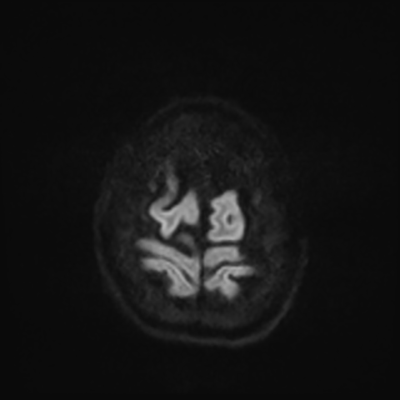

MRI brain (DWI)

MRI brain (DWI) 1/24 1/24

You can clearly see diffuse cortical and basal ganglia diffusion restriction, and that of his deep cerebellar nuclei as well. The right occipital lobe abnormalities are a little more prominent, but then you remember that he is known to have had a right occipital stroke weeks ago.

In reviewing his data, you know that he doesn't have any of the strong predictors of a poor neurologic prognosis. However, based on these findings on MRI, along with the absent reactivity on cEEG, you are able to tell the primary team and the patient's family that he is likely to have a poor prognosis, based on these multiple moderate predictors. Recovery is not completely impossible-- there is more uncertainty with this prognostication than if we were able to get SSEPs-- but you're very worried about his outlook and that any potential recovery would require a very protracted rehabilitation period. Given his high cervical cord injury level, tracheostomy would be required anyway. So, it comes down to whether his family thinks he'd want to pursue these aggressive measures.